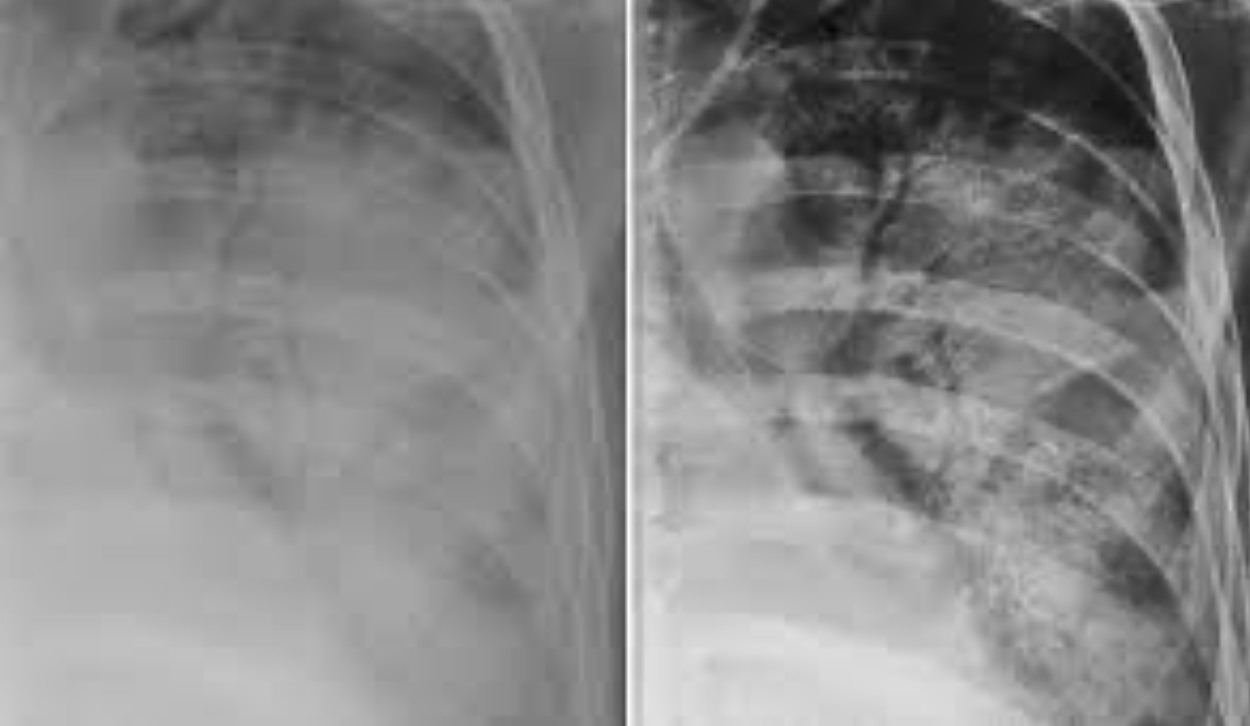

Consolidación alveolar

How well did you know this?

1